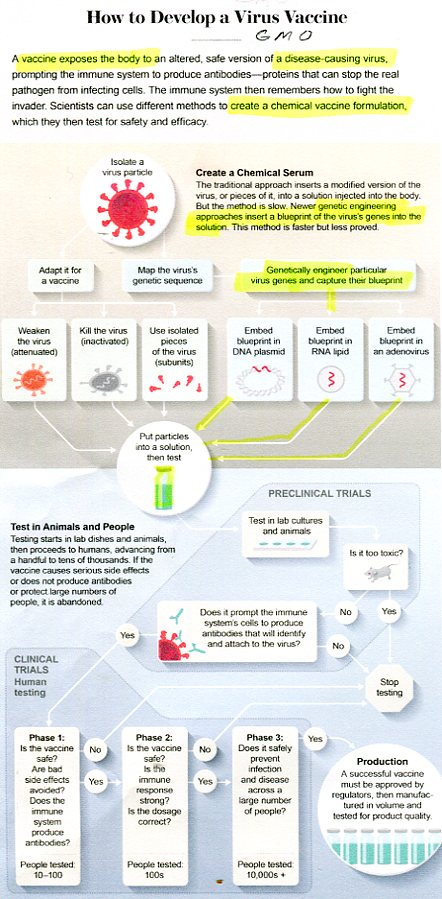

COVID INJECTS GMO TRACKING DEVICE

Genetically Engineered COVID Vaccine Being Made

COVID-19 AGENDA CERTIFICATE OF VAX ID BY AI

Scientific American, Dec 3, 2021